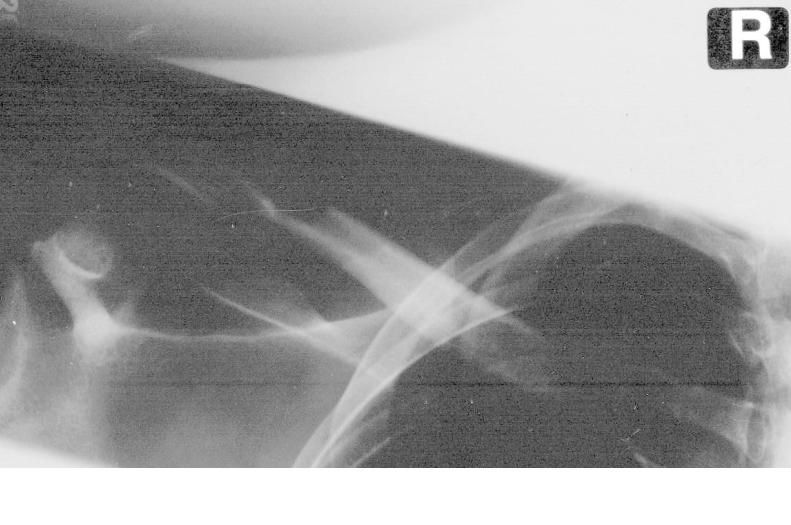

tja mich hats gestern erwischt. Schotter in einer Kurve

Ich hab so einen Kreutzverband bekommen, nun weiss ich nicht wie fest ich den machen sollte. Im Liegen spüre ich den kaum und die Schmerzen halten sich in Grenzen. Wenn ich aber sitze, dauert es keine 10 Miuten und es fängt an übler weh zu tun, wenn ic mich dann wieder lege, knuspelt es lecker in der Schulter und dann wirds wieder besser...